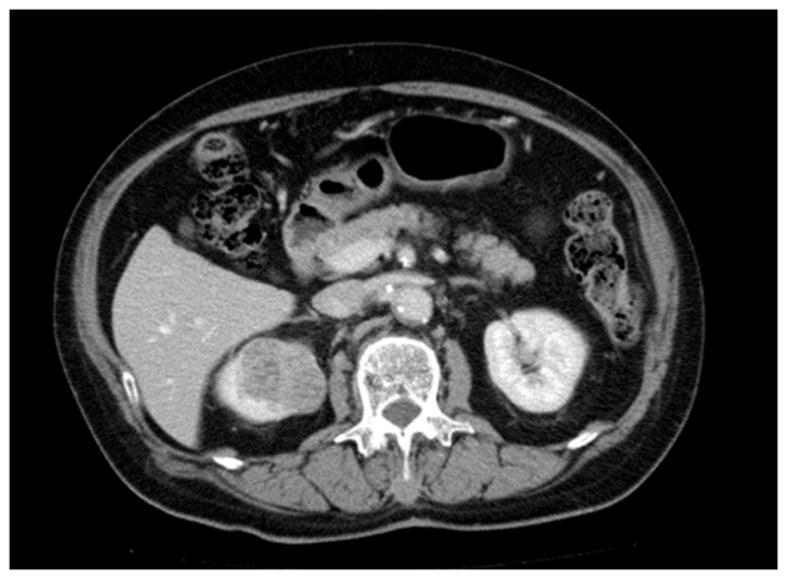

Mucinous tubular and spindle cell carcinoma (MTSCC) is a relatively rare renal epithelial neoplasm. Although MTSCC is considered to be a low-grade and indolent neoplasm, aggressive cases have been recently reported. The present study discussed two additional cases of high-grade MTSCC causing multiple distant metastases with a fatal course. In case 1, a 71-year-old patient presented with hematuria and pyuria. Computed tomography (CT) scan of the right kidney revealed a mass lesion, for which partial nephrectomy was performed. However, a follow-up CT imaging revealed distant metastases in the liver, the paraaortic lymph nodes and the bone. Despite molecular targeted therapy and irradiation, the patient succumbed due to tumor progression. In case 2, a 64-year-old patient presented with an incidentally identified mass lesion in the right kidney. A laparoscopic nephrectomy was performed, and a follow-up CT imaging revealed metastases in the skin and lungs. The cytology of pleural effusion revealed pleuritis carcinomatosa. Histologically, both cases were diagnosed as mucin-poor MTSCC with high-grade transformation, which comprised uniform tumor cells primarily forming slender tubules. The tumors contained low- and high-grade regions. In addition, venous invasion and necrosis were observed. The tumor cells also demonstrated increased Ki-67 labeling indices and cellular tumor antigen p53 (p53) nuclear accumulation. High-grade transformation, large tumor size, necrosis, venous invasion, high Ki-67 labeling index and p53 nuclear accumulation are generally predictive findings for aggressive behavior of malignant tumors. In the current report, it was emphasized that MTSCC possesses a wide spectrum of clinicopathological features. Thus, careful postoperative investigation is required for MTSCC with high-grade elements due to its aggressive nature.

黏液性小管状和梭形细胞癌(MTSCC)是一种相对罕见的肾上皮性肿瘤。尽管MTSCC被认为是一种低级别、惰性肿瘤,但最近有侵袭性病例的报道。本研究讨论了另外两例高级别MTSCC导致多发远处转移并呈致命病程的病例。病例1,一名71岁患者出现血尿和脓尿。右肾计算机断层扫描(CT)显示有一个肿块病变,为此进行了部分肾切除术。然而,后续CT成像显示肝脏、腹主动脉旁淋巴结和骨骼有远处转移。尽管进行了分子靶向治疗和放疗,患者仍因肿瘤进展而死亡。病例2,一名64岁患者偶然发现右肾有一个肿块病变。进行了腹腔镜肾切除术,后续CT成像显示皮肤和肺部有转移。胸腔积液细胞学检查显示为癌性胸膜炎。组织学上,两例均诊断为伴有高级别转化的黏液缺乏型MTSCC,由主要形成细长小管的均匀肿瘤细胞组成。肿瘤包含低级别和高级别区域。此外,观察到静脉侵犯和坏死。肿瘤细胞还显示Ki-67标记指数增加和细胞肿瘤抗原p53(p53)核积聚。高级别转化、肿瘤体积大、坏死、静脉侵犯、高Ki-67标记指数和p53核积聚通常是恶性肿瘤侵袭行为的预测性表现。在本报告中,强调了MTSCC具有广泛的临床病理特征。因此,由于其侵袭性,对于伴有高级别成分的MTSCC,术后需要仔细检查。